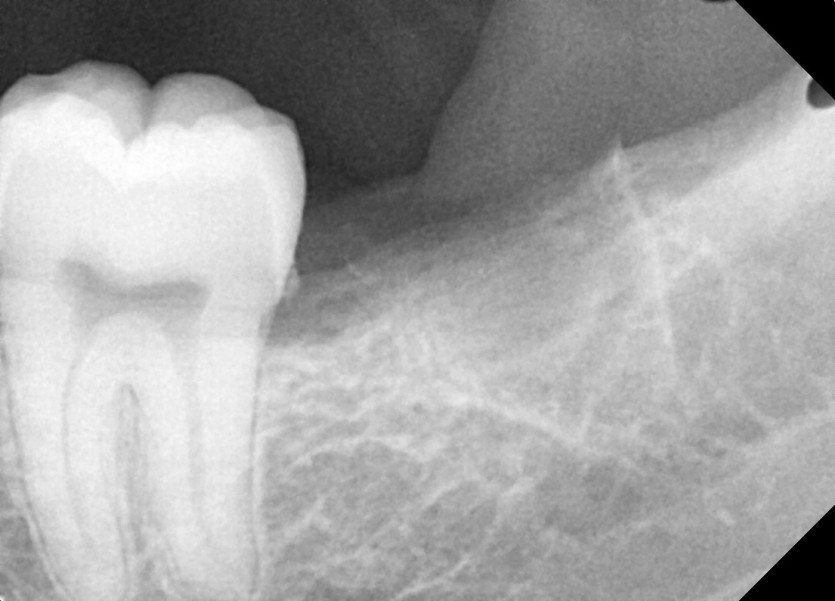

#38 사랑니 발치

구강 외과 전문의가 당일 발치했습니다.